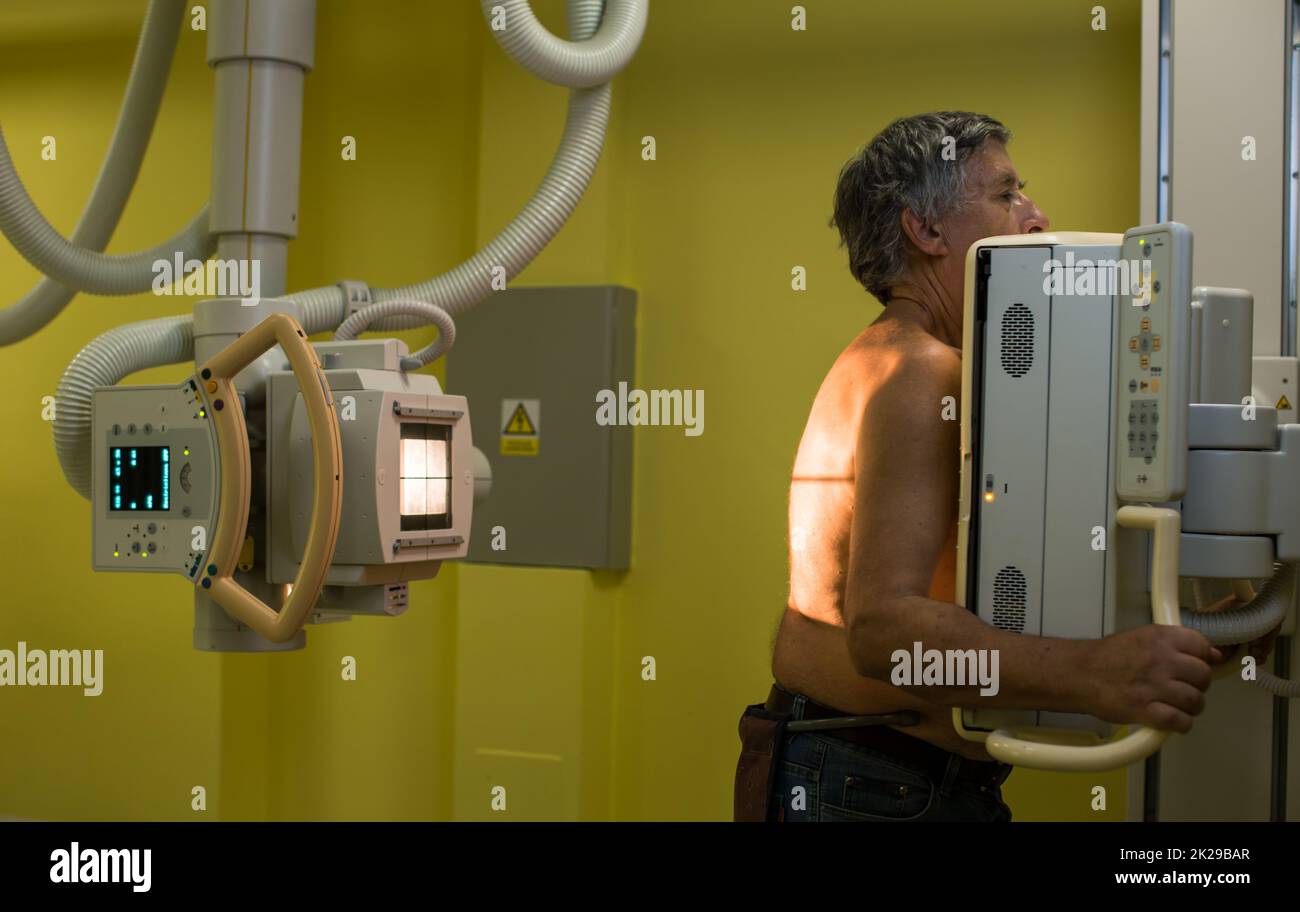

Senior man x-ray medical scan examination in a modern hospital (color toned image) Stock Photohttps://www.alamy.com/image-license-details/?v=1https://www.alamy.com/senior-man-x-ray-medical-scan-examination-in-a-modern-hospital-color-toned-image-image483326106.html

Senior man x-ray medical scan examination in a modern hospital (color toned image) Stock Photohttps://www.alamy.com/image-license-details/?v=1https://www.alamy.com/senior-man-x-ray-medical-scan-examination-in-a-modern-hospital-color-toned-image-image483326106.htmlRF2K29BAJ–Senior man x-ray medical scan examination in a modern hospital (color toned image)

Senior man x-ray medical scan examination in a modern hospital (color toned image) Stock Photohttps://www.alamy.com/image-license-details/?v=1https://www.alamy.com/senior-man-x-ray-medical-scan-examination-in-a-modern-hospital-color-toned-image-image483326111.html

Senior man x-ray medical scan examination in a modern hospital (color toned image) Stock Photohttps://www.alamy.com/image-license-details/?v=1https://www.alamy.com/senior-man-x-ray-medical-scan-examination-in-a-modern-hospital-color-toned-image-image483326111.htmlRF2K29BAR–Senior man x-ray medical scan examination in a modern hospital (color toned image)